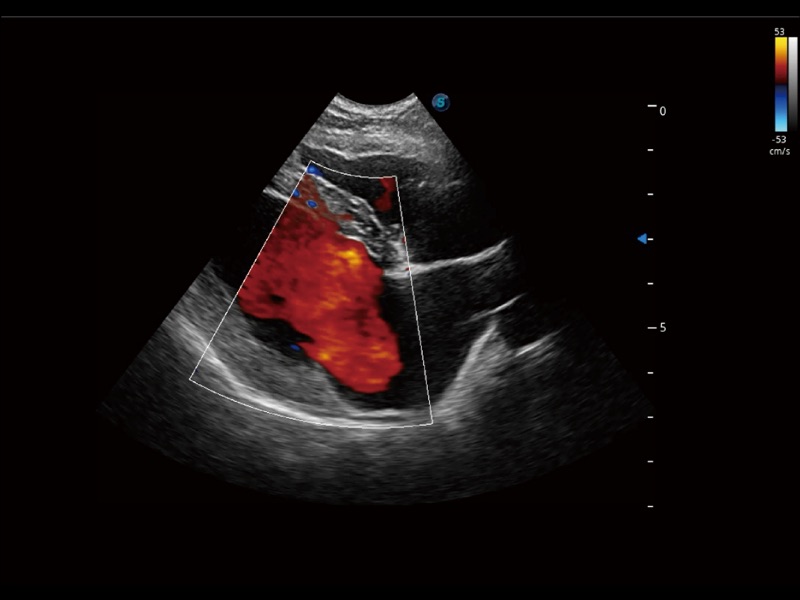

(犬)左室长轴血流